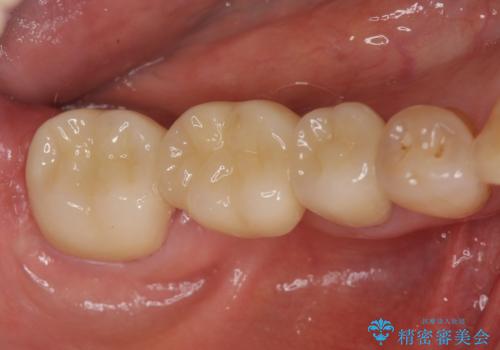

抜歯を行ったのち前後の歯に軽度の動揺があるため、インプラントではなくブリッジによる補綴処置を行い機能回復を行いますが、近心傾斜した第2大臼歯をマイクロインプラントを用いた小矯正を行うことで歯軸方向を改善し、神経を温存した状態でブリッジ製作できるよう前処置を行います。

ブリッジが長く機能できるように噛み合わせの微細な調整は非常に大切ですが、支台となる歯の神経を温存できるかどうかも非常に大きな要因です。

今回の治療ではブリッジ製作に先んじて小矯正を行うことで、より予知性を高める治療をおこなうことができました。